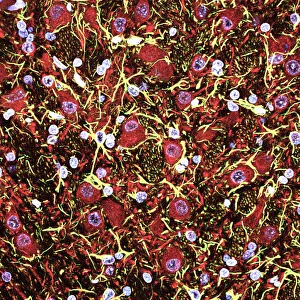

The central nervous system, the intricate network that governs our every thought and movement, is a marvel of complexity. From the delicate cerebellum tissue to the detailed light micrograph capturing its essence, we are reminded of its importance in maintaining balance and coordination. Anatomy comes alive as we explore the human brain from an inferior view. The intricacy of brain fibers is revealed through DTI MRI scans like C017/7099 and C017/7035, showcasing their vital role in transmitting information throughout this extraordinary organ. Artistic renderings bring us closer to understanding the medulla oblongata's significance within the brain. Its portrayal in various artworks allows us to appreciate how it controls essential functions such as breathing and heart rate. As we delve deeper into studying the central nervous system, models of the human brain provide invaluable insights into its structure and organization. Lateral views reveal countless regions responsible for cognition, emotion regulation, sensory perception, and motor control. Microscope slides offer glimpses into nerve cells' intricate architecture—a testament to their ability to transmit electrical signals at lightning speed. Meanwhile, glial stem cell cultures captured under a light microscope remind us of their crucial role in supporting neuronal function. Finally, artistic representations unveil the limbic system's enigmatic nature—an interconnected web responsible for emotions and memory formation. These captivating artworks allow us to visualize this complex network within our brains. Exploring these hints provides a glimpse into the awe-inspiring world of our central nervous system—the very foundation upon which our thoughts, actions, memories reside—reminding us just how remarkable our brains truly are.